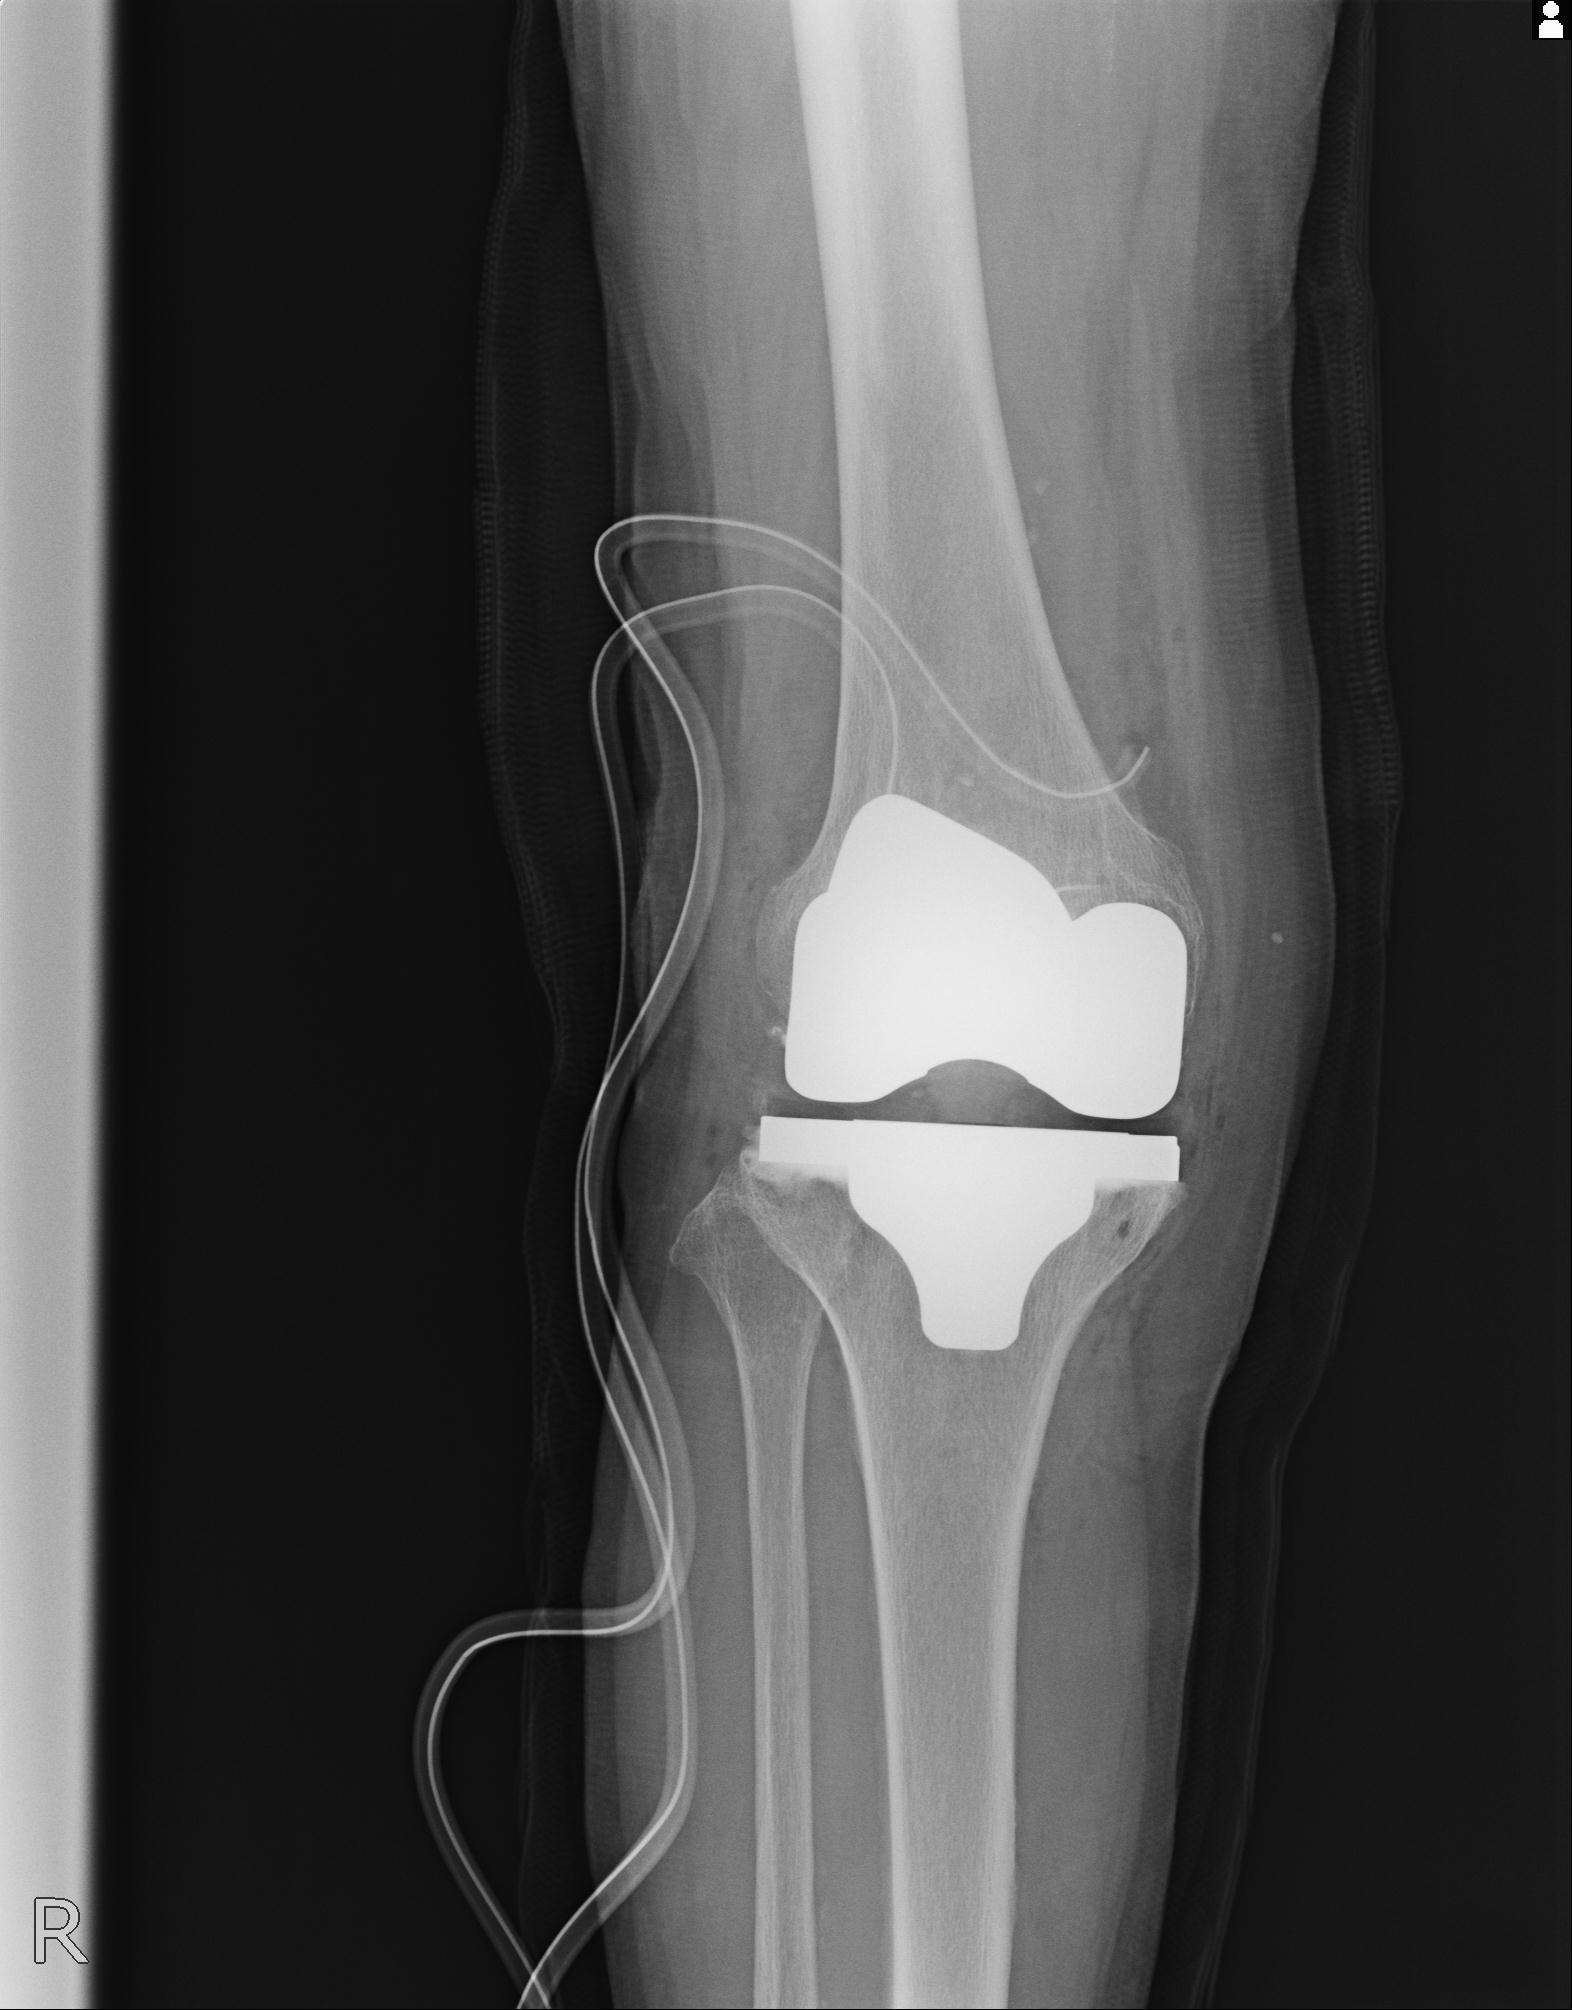

100612 11/25 1/20 右膝 2R 84歳女性 右TKA